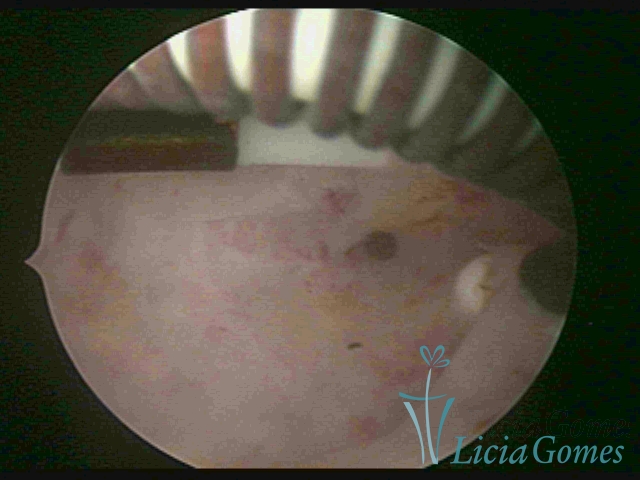

Cervical canal with IUD string